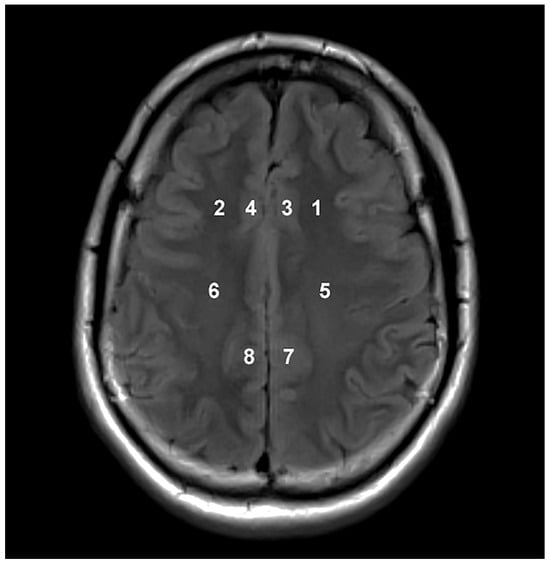

| Location | Metabolite Concentrations and Ratios | Groups Categorized According to Disease Severity | Contribution % | ||

|---|---|---|---|---|---|

| Mild | Moderate | Severe | |||

| 1 | Cr | 6.469 *2 | 5.827 *1 | 5.233 | 50.333 |

| NAA | 9.535 *2 | 8.902 *1 | 8.291 | 29.333 | |

| Cho/NAA | 0.666 | 0.701 | 0.739 *1 | 8.000 | |

| 2 | Cr | 6.517 *2 | 5.973 *1 | 5.321 | 37.652 |

| NAA | 10.075 *2 | 9.384 *1 | 8.502 | 28.340 | |

| Cho/Cr | 1.181 | 1.284 *1 | 1.390 *2 | 17.814 | |

| 3 | Cho | 1.783 *1 | 1.651 | 1.550 | 42.105 |

| Cho/NAA | 0.756 | 0.801 | 0.846 *1 | 24.342 | |

| Cr | 6.743 *2 | 5.891 *1 | 5.133 | 11.842 | |

| 4 | Cho/NAA | 0.760 | 0.784 | 0.839 *1 | 38.767 |

| Cr | 6.910 *2 | 5.833 *1 | 5.274 | 26.872 | |

| NAA | 7.700 *2 | 6.716 *1 | 6.099 | 14.978 | |

| 5 | Cho/NAA | 0.534 | 0.571 | 0.599 *1 | 22.131 |

| NAA | 12.075 *2 | 10.631 *1 | 9.671 | 20.765 | |

| Cr | 6.028 *2 | 5.482 *1 | 4.894 | 18.852 | |

| 6 | Cr | 6.398 *2 | 5.822 *1 | 5.133 | 36.842 |

| NAA | 12.848 *2 | 11.631 *1 | 10.054 | 22.601 | |

| Cho | 2.082 *1 | 1.979 *1 | 1.773 | 18.576 | |

| 7 | Cr | 7.199 *2 | 7.054 *1 | 6.141 | 42.246 |

| Cho | 2.033 | 2.051 | 1.982 | 26.738 | |

| NAA | 11.706 *1 | 10.895 *1 | 9.303 | 14.973 | |

| 8 | Cr | 7.248 *2 | 6.600 *1 | 6.017 | 35.821 |

| Cho | 2.069 | 2.055 | 1.887 | 32.537 | |

| NAA | 11.411 *1 | 10.454 *1 | 8.920 | 21.493 | |